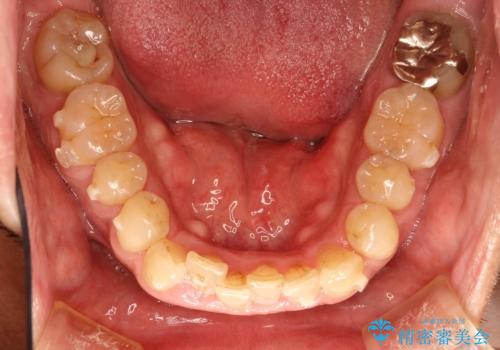

インビザライン invisalign ガタつきを治すマウスピース矯正

- 非抜歯・上顎臼歯遠心移動によるマウスピース矯正を計画した。

ガタつきを取り除くだけであれば非常に簡潔であるマウスピース矯正ですが、奥歯の位置関係の是正や、垂直的な歯の位置のコントロールなどが計画に含まれる場合、治療が難しくなってきます。